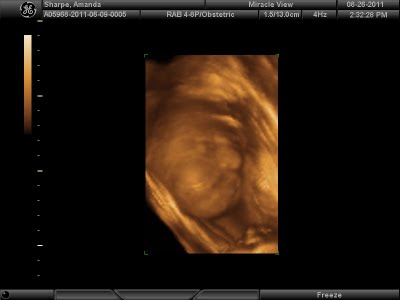

Images of Our Little Peanut

We get to "see" Peanut today!!